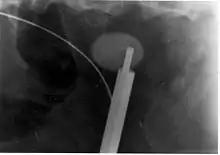

A kidney stone at the tip of an ultrasonic stone disintegration apparatus

More definitive ureteroscopic techniques for stone extraction (rather than simply bypassing the obstruction) include basket extraction and ultrasound ureterolithotripsy. Laser lithotripsy is another technique, which involves the use of a holmium:yttrium aluminium garnet (Ho:YAG) laser to fragment stones in the bladder, ureters, and kidneys.[103]